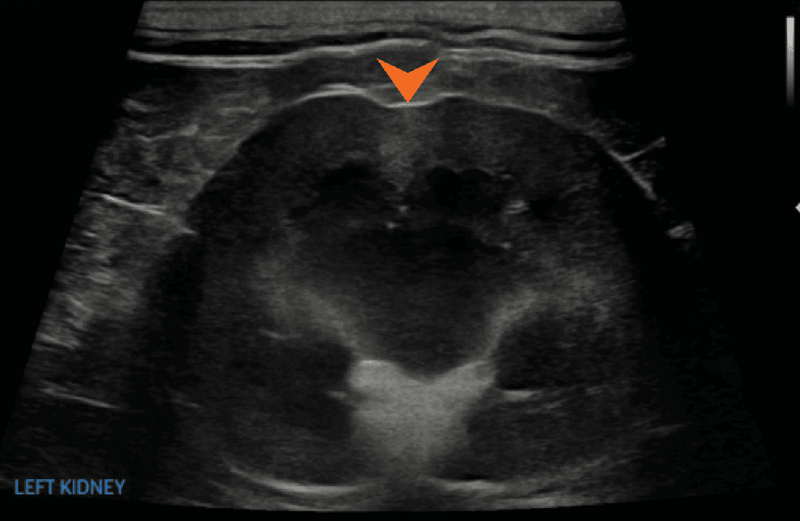

Zawały w nerkach (ryc. 13) najczęściej dotyczą kory nerek. Ich liczba oraz wielkość mogą być różne.8,17 Są one związane nie tylko z przewlekłą chorobą nerek, lecz także z innymi przyczynami, takimi jak zaburzenia krzepnięcia, sepsa albo nowotwory.8 Często wskazane jest wykonanie badań serologicznych w celu potwierdzenia rozpoznania.3 Zawały kory nerkowej przyczyniają się również do nieregularności obrysu nerki, rzadko jednak obejmują więcej niż dwie trzecie miąższu nerkowego, dlatego zwykle nie są jedyną klinicznie istotną przyczyną utraty czynności nerek.17 Cechy ultrasonograficzne zawałów nerek mogą się różnić w zależności od tego, czy są to zmiany ostre, czy przewlekłe.22 Po doświadczalnym ogniskowym zamknięciu gałęzi tętnicy nerkowej w ciągu 24 godzin stwierdzono ogniskowy obrzęk i hipoechogeniczność kory nerkowej, które utrzymywały się przez 5-7 dni.21 W tym badaniu po siedmiu dniach echogeniczność dotkniętego obszaru stopniowo wzrastała, a około 17. dnia obserwowano stopniowo kurczącą się, klinowatą zmianę z wklęsłym ubytkiem wzdłuż brzegu torebki nerki.

Ryc. 13. Obraz w projekcji strzałkowej lewej nerki kota, ukazujący słabo odgraniczony, klinowaty obszar zwiększonej echogeniczności w korze oraz położony poniżej mały wklęsły ubytek wzdłuż brzegu torebki (grot strzałki), co odpowiada przewlekłemu zawałowi kory nerki.